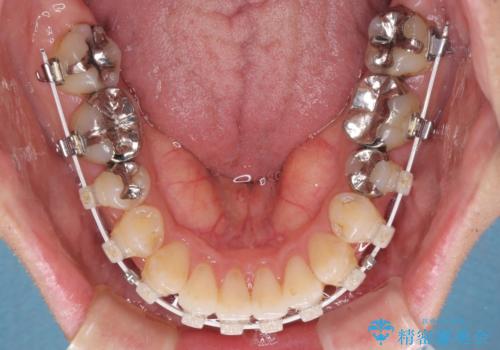

上顎奥歯付近にアンカースクリューを用い、上顎歯列全体の後方移動と、大臼歯圧下を促し、前歯の上下関係を改善することとしました。

奥歯には目立つ銀歯が多くあるので、矯正治療後には下顎の銀歯をセラミッククラウンやセラミックインレーにより、補綴・修復治療することとしました。

上顎歯列全体を後方に移動させたため、口元の突出感も改善され、装置を外してからは口が閉じやすくなりました。

また、上下犬歯が接触するようになったため、奥歯にストレスのかからない歯ぎしりができるようになり、顎の疲れも改善されました。